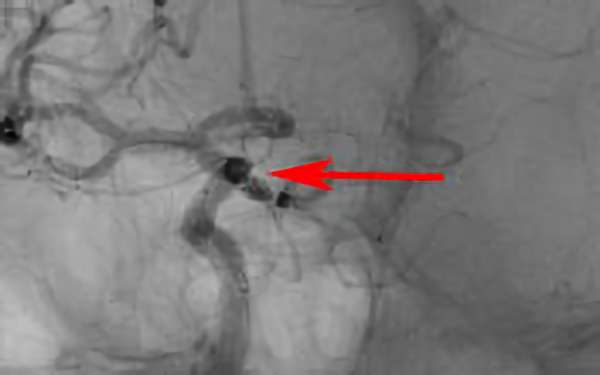

No.1630 手術前